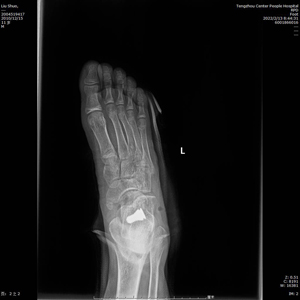

術(shù)中C型臂透視見:制動器位置良好,模擬左足負(fù)重試驗(yàn),患者足弓恢復(fù)良好。整個手術(shù)時間短,創(chuàng)傷小,見效快,僅用時30分鐘,微創(chuàng)刀口1cm,出血量不足5ml。術(shù)后左足石膏固定,2天后出院。?

(術(shù)后X線)